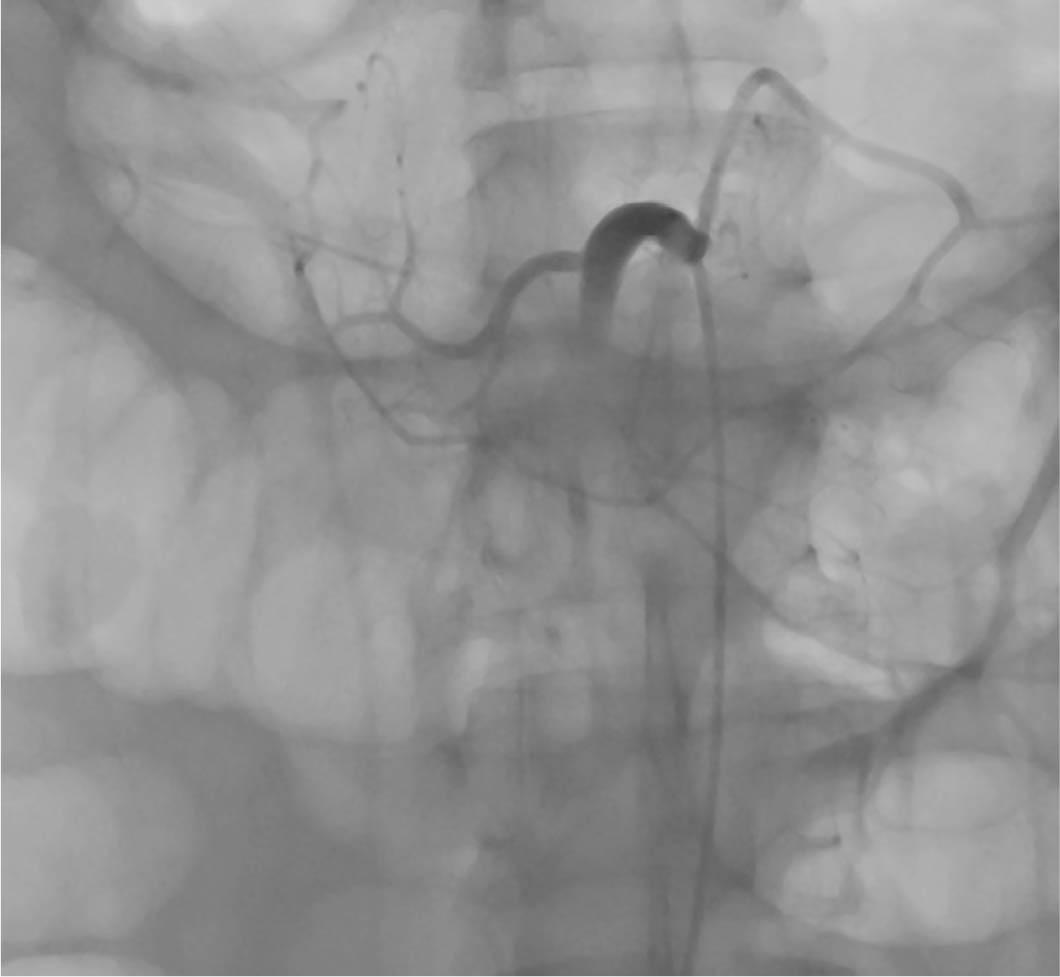

Figure 1